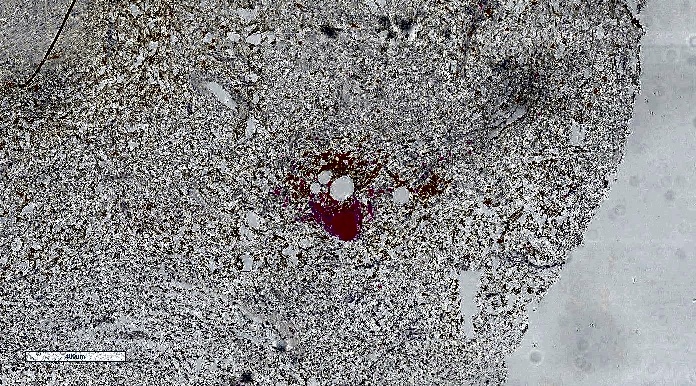

原始图像的屏幕截图:

原件: